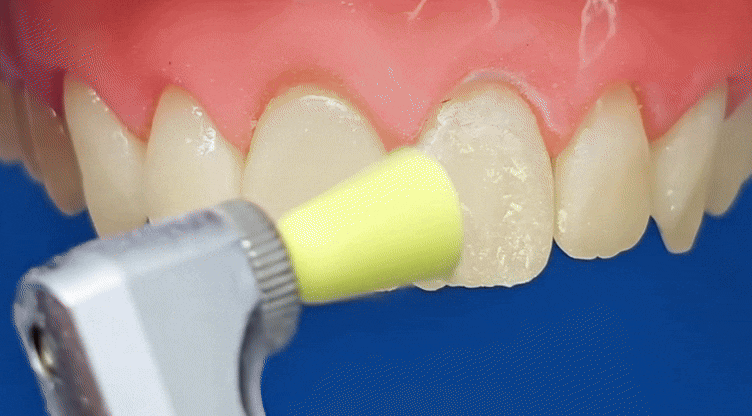

이럴 때는

새로 레진을 하기 보다는

눈에 띄는 겉면만

폴리싱(연마, 다듬기)으로 정리해도

변색된 부분을 충분히 지울 수가 있습니다.

폴리싱은

충치를 제거할 때 쓰는

강한 다이아몬드 버로 깎는 과정이 아니라,

화이트 스톤 버와 같은

미세한 연마 도구를 이용해

표면을 부드럽게 닦아내는 과정에 가깝습니다.

치아의 겉껍질인

법랑질은 그대로 두고,

상대적으로 더 부드러운 레진 표면만

정리해 주는 방식입니다.